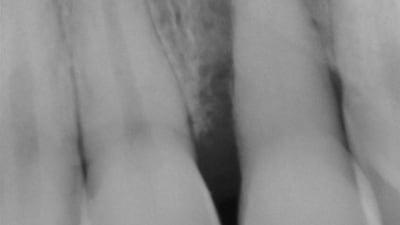

Online Only Online Only Accuracy of CBCT Versus Periapical Radiography Measurements When Planning Placement of Implants in the Posterior Maxilla By Adam Barsoum, BDS, Stuart J. Froum, DDS, Takahito Kakumoto, DDS July 15, 2021 12 min read